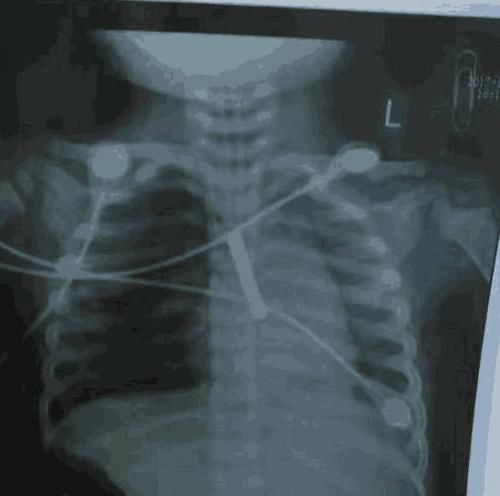

日前看到这样的一则新闻,让人很是心痛:一岁5个月的孩子在家玩耍时突然倒地,家人将孩子送往医院抢救,但是到达医院的时候孩子已经没有了心跳和呼吸,在医护人员的极力抢救之下孩子恢复了心跳,但是仍然处于昏迷状态,甚至出现窒息休克的症状。顺德勒流医院联系了广东医科大学附属妇女儿童医院的专家一起会孩子进行会诊,X光片完善以后让所有的人员都惊呆了,X光片显示在孩子的气管内有异物,正因为异物堵塞气管,导致孩子无法正常呼吸。尽管医生已经很尽力了,但是孩子由于长时间缺氧,导致机体的多个器官受到了严重的损伤,孩子最终还是没能抢救回来。